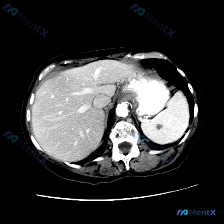

最近看到一份腹部平扫CT的影像资料,主要异常集中在脾脏,整理了一下读片和分析思路,和大家分享。 先整理一下核心影像事实 这是一张腹部CT软组织窗横断面图像,主要发现如下: 1. 肝脏:实质密度尚均匀,未见明确局灶性占位,肝叶比例、血管走行基本正常 2. 脾脏:形态正常,但脾实质内可见一个圆形、边界相...

最近看到一份影像资料,觉得很适合用来聊一聊读片时的“预期与证据不符”以及影像局限性的问题,整理了一下思路和大家分享。 病例/影像背景 用户的疑问是“图中识别到的异常是什么?脾脏病变”,提供的是一张腹部增强CT横断面(肝门区及胃底水平)的图像描述。 关键影像所见(整理自描述) 脾脏:形态正常,密度均匀...